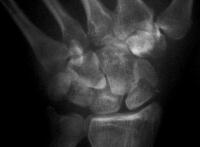

Case 5. Another,same bidirectional technique. Here, I ran the second screw too close to the first, and may have flattened the leading threads - not

ideal. The preop status:

With intercalated iliac bone graft...

and healing.